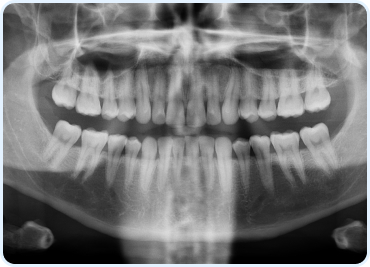

Full Arch Perspective: The OPG technology delivers a full panoramic view of the oral cavity, revealing the teeth, jawbone, and sinus anatomy in a single image.

Automated Analysis: Features software that can automatically highlight and analyze areas of concern, such as potential bone loss or the presence of foreign objects.

3D Reconstruction Capability: Some OPG systems offer 3D reconstruction options for a multi-dimensional view of the oral anatomy, which is crucial for complex implant procedures.